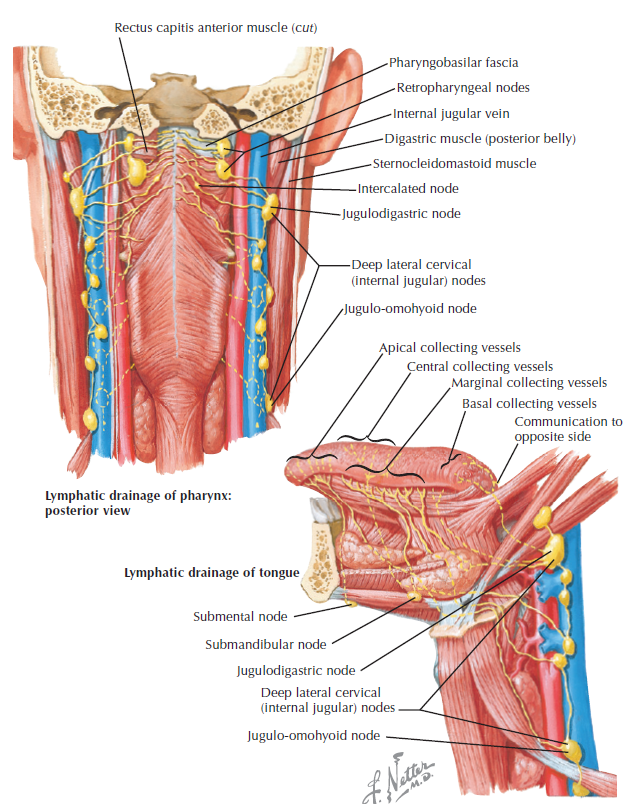

Lymphatic system

總圖

Nodes

Lingual Lymphatic nodes

病灶

Tongue

Tonsil

用vocal fold 分,上,下分別到SDC, IDC